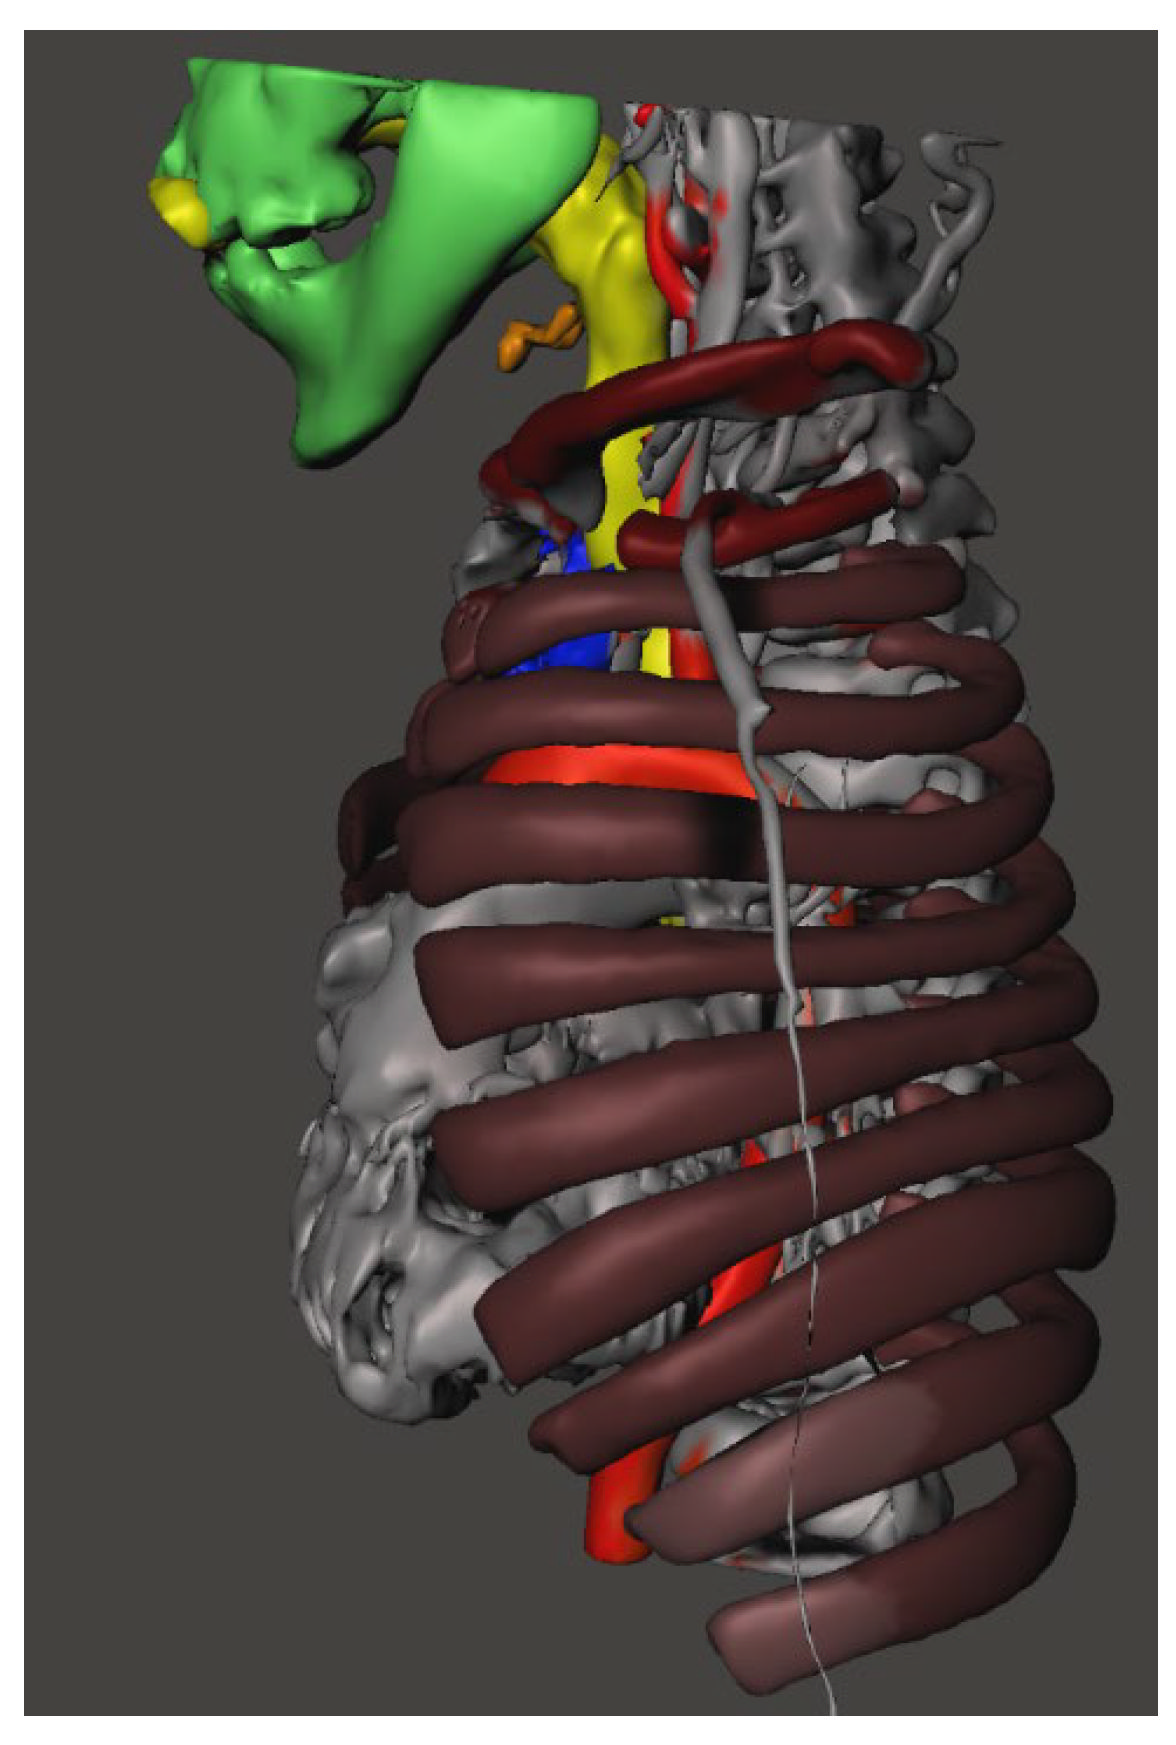

2. Ethical Issues

3. Case Presentation

4. Discussion